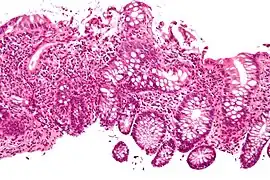

Cryptitis. H&E stain.

Crypt abscess. H&E stain.